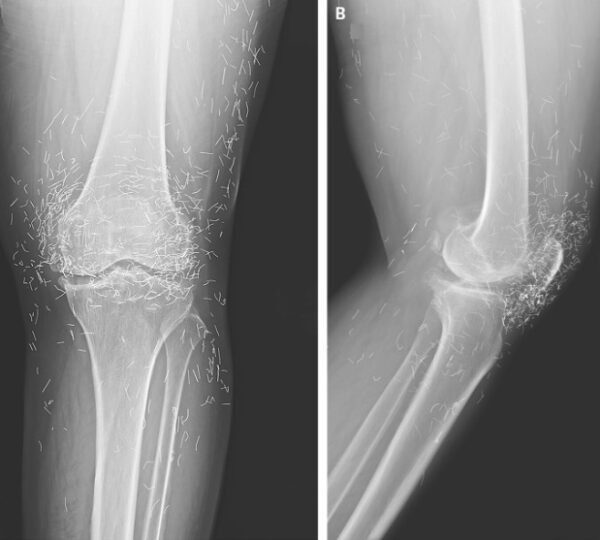

In this woman’s case, imaging studies revealed multiple gold needles embedded deep within her knee joints. Radiologists were surprised by the density and number of retained objects, which created both clinical interest and concern.

In her case, the needles—believed to be gold—were left inside her knees intentionally. This practice, known as intradermal or retained acupuncture, is intended to provide continuous stimulation to the joint and prolong therapeutic effects.

In South Korea, inserting tiny sterile gold threads around a joint is a traditional treatment for osteoarthritis. This method is thought to stimulate blood flow, promote healing, and reduce pain, although rigorous scientific validation is still lacking.

Modern imaging techniques, including X-rays and MRIs, can detect these embedded needles. Radiologists must consider retained metal when interpreting images, as it can interfere with diagnostic clarity and obscure underlying conditions.

The case has drawn attention in medical literature, including the New England Journal of Medicine, as an unusual example of retained gold needles and the potential complications associated with alternative therapies for osteoarthritis.